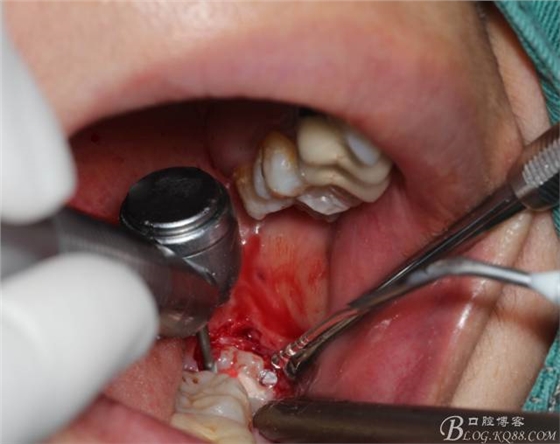

補(bǔ)完牙后,準(zhǔn)備撥除阻生智齒了。

先分析智齒的情況,口內(nèi)直觀是半個(gè)牙尖都沒露出來,差一點(diǎn)就完全埋伏了。磨牙后墊的可操作面積中規(guī)中紀(jì),X全景片示三類阻生,根冠比例是1:1,非融合根,近中根壓下頜管。

640 (6).jpg

切開:角形切口,這個(gè)位置切開我喜歡更易操作12#刀。

640 (8).jpg

鈍性翻辨露冠

640 (10).jpg

角度鍋輪機(jī)結(jié)合冷鹽水冷卻分冠

640 (11).jpg

分冠完成

640 (12).jpg

取出阻力部分冠

640 (13).jpg

在取出阻力冠后,嘗試性看能取出全部的牙體不,就是取不出也能整體撬動(dòng)牙根。